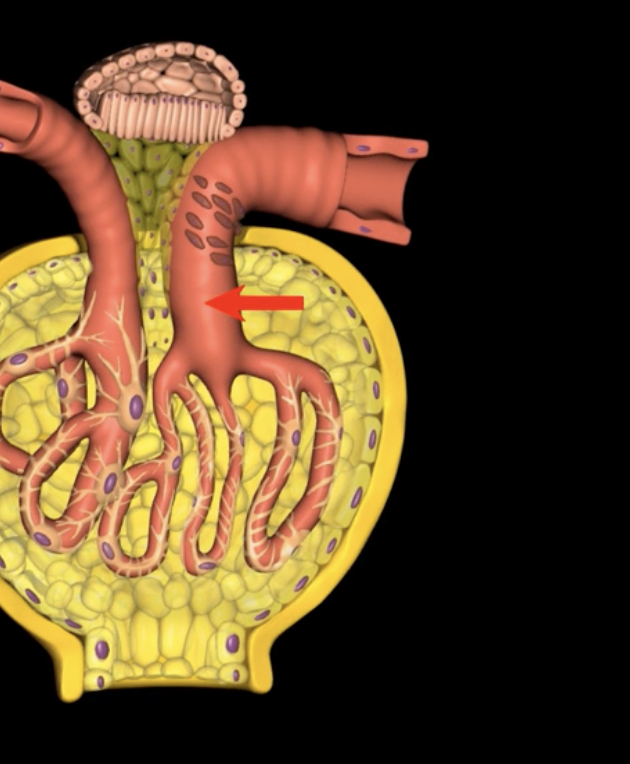

Elevated Glomerular hydrostatic pressure (GHP) promotes … red arrow

proteins that remain in the glomerulus create glomerular oncotic pressure, which has a tendency to pull fluid back into the glomerular capillaries

Blood colloid osmotic pressure (HPc): red arrow

Filtrate with bowman’s capsule exerts capsular hydrostatic pressure which impedes additional movement of fluid from the glomerular capillaries into the capsular space

capsular hydrostatic pressure (HPc): red arrows